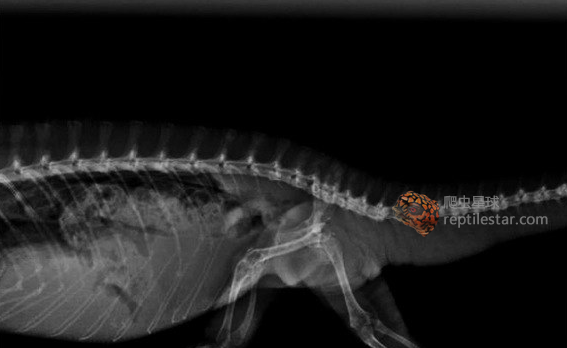

有人会在笼内对吃剩的蟋蟀进行回收,但千万不要把凝胶晶体这类饲料放在笼内,变色龙误食会导致肠道扩张,引发死亡。